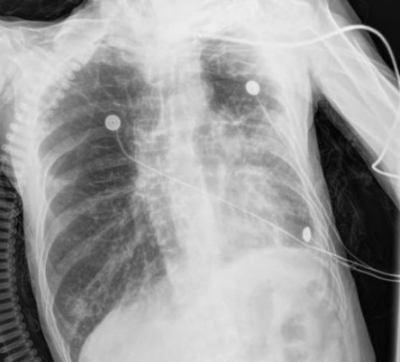

呼吸与危重症医学科救治。该科副主任朱锦琪、梁伟军及团队高度警觉免疫治疗病史可能带来的并发症,详细追溯他两年的免疫治疗用药记录,对其近期肺部CT影像进行反复对比和深入研判,认为其符合免疫检查点抑制剂相关肺炎(CIP)的典型表现,确诊其为迟发性、重度(4级)免疫检查点抑制剂相关肺炎。

免疫检查点抑制剂相关肺炎4级

明确诊断后,患者的治疗迎来关键转折点,团队迅速调整方案,启动大剂量糖皮质激素抗炎治疗,治疗效果立竿见影。患者的病情显著改善,氧合指数稳步上升,呼吸困难症状明显缓解。经过精心治疗,他在进入呼吸重症监护室一周后便转入呼吸科普通病房;10天后复查胸部CT,显示肺部弥漫性病变明显吸收好转,顺利出院。后续的定期随访复查也证实其肺部状况持续向好。